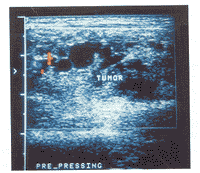

腸道血管畸形超聲圖片1.消化性潰瘍本病為慢性、周期性發作的疾病,常表現為節律性疼痛,伴反酸、噯氣,多於秋冬、春季發作,鋇餐、內鏡及血管造影檢查等可與血管畸形鑑別。